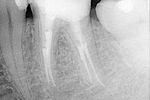

Revisionsbehandlung eines Unterkiefermolaren (37) vor geplanter Überkronung (Dr. Maik Göbbels) Download